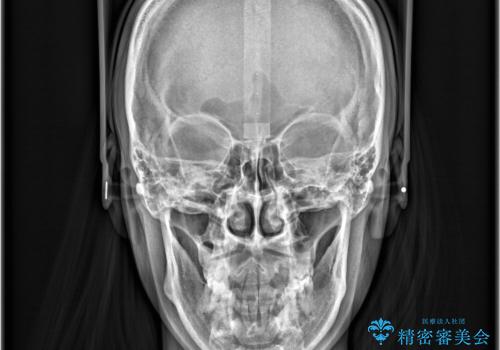

- 八重歯と口元が出ていることを主訴に来院されました。

レントゲンの検査において、前歯も外側に傾いてる結果であったため、上下左右の小臼歯を抜歯して配列を行いました。

歯の動きも良く短期間で治療を終えられたため患者さんにも大変満足していただきました。